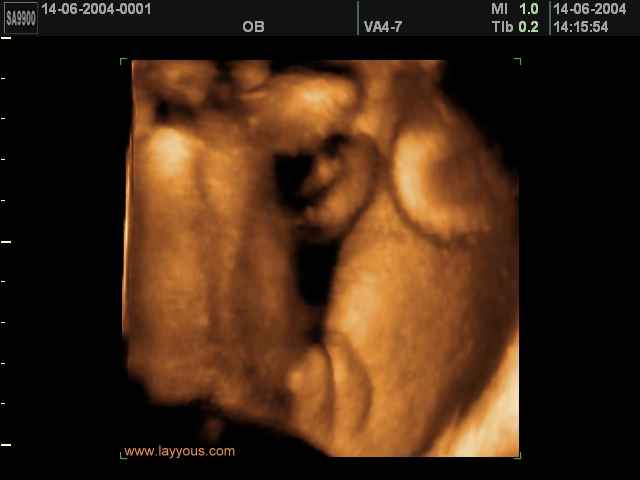

- لقطات فيديو للجنين بجهاز الموجات فوق صوتية رباعي الأبعاد

- صور لوجه الجنين في داخل الرحم

- صور لتصرفات الجنين داخل الرحم

صور لأعضاء الجنين بجهاز الموجات فوق صوتية ثلاثي الأبعاد | الدكتور نجيب ليوس